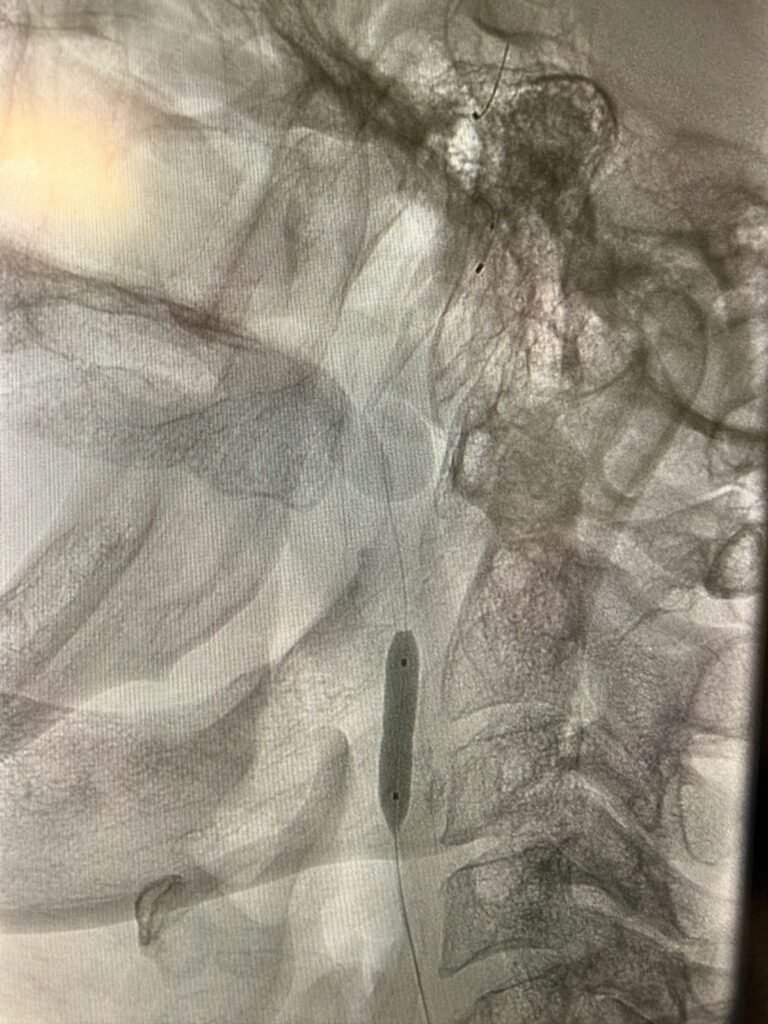

El procedimiento endovascular de alta complejidad está destinado a tratar la estenosis de las arterias carótidas y prevenir accidentes cerecerebrovasculares (ACV).

Mediante un abordaje percutáneo por arteria femoral, utilizamos filtros de protección cerebral para minimizar el riesgo de embolias durante la intervención. Posteriormente, efectuamos la dilatación con balón y la colocación de un stent de celdas cerradas, logrando una revascularización segura y eficaz, sin necesidad de cirugía a cielo abierto.